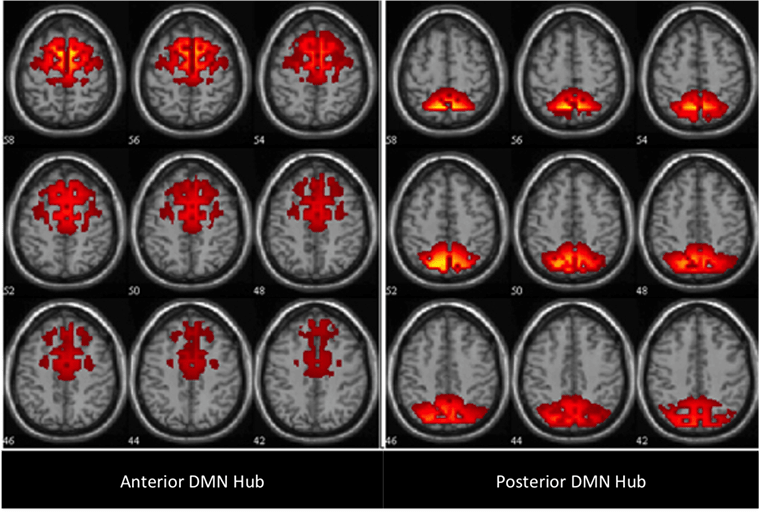

While the EEG is a very different measure from fMRI, it does measure signals from some regions involved in the DMN, providing an overlapping albeit distinct view of brain activity. These include the anterior and posterior DMN hubs in the cortex (shown as axial sections in the image above). Particularly it is the alpha band activity of the EEG (activity in one frequency range of the electrical siganl) that is most correlated to DMN activity (Knyazev GG et al, 2011 ). To the extent that the EEG can read aspects of DMN activity, it makes access less expensive, easier to use and very nearly consumer-friendly.

Second, these areas, and their affiliated DMN, are functionally different. Specially, the anterior hub, which comprises the medial prefrontal cortex, is thought to be more involved in complex social relations and is often accompanied by negative emotions. In contrast, the posterior hub is more involved in self-centered cognition (e.g., ongoing self-monitoring) and generally accompanied by positive emotions.